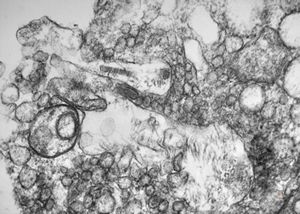

M, 62y. | angiomatous tumor, v.s. Kaposi sarcoma

M, 62y. | Weibel-Palade body - angiomatous tumor, v.s. Kaposi sarcoma